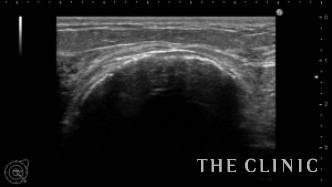

10年前に脂肪注入を受けられ、大きなしこりが出来たとのことで当院へご相談にご来院されました。触診では右に5㎝、左に6㎝の硬いしこりを触知し、エコーでは乳腺下に石灰化したしこりを認めました。

石灰化していなければ、大きな傷をつくることなく治療できますが、この症例は完全に石灰化しているため、切開して摘出するしかありません。乳輪に沿った傷ですので、ほとんど傷跡は判らなくなります。摘出したしこりです。

割面です。しこりは、完全に石灰化した被膜に覆われ、内部は壊死した脂肪で詰まっていました。